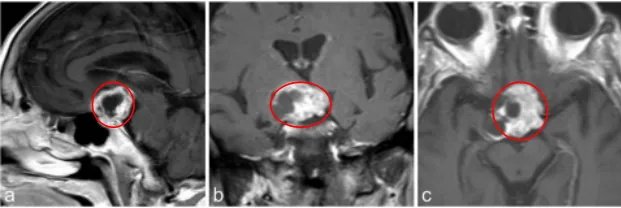

7岁男孩出现垂体功能减退的症状,如体重减轻、生长发育停滞、身体状况不佳和疲劳。就诊四周前,他一直抱怨头痛和呕吐,评估表明是全垂体功能减退。

a–c图MR成像显示囊性病变对比增强,高度怀疑颅咽管瘤

j、k、l图显示,肿瘤得到全切